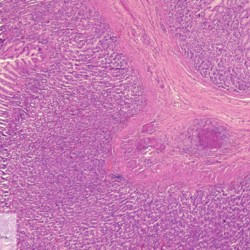

Etiquetes: N-90/90 de 2 Pàgina següent 9 total Canine Specie: Canine Organ: Stomach Lesion: Vasculitis Lesion modifier: - Disease: Leishmaniasis Files/Expedient: N-90/90 Not viewed Canine Specie: Canine Organ: Stomach Lesion: Vasculitis Lesion modifier: - Disease: Leishmaniasis Files/Expedient: N-90/90 Not viewed Canine Specie: Canine Organ: Intestine Lesion: Vasculitis Lesion modifier: - Disease: Leishmaniasis Files/Expedient: N-90/90 Not viewed Canine Specie: Canine Organ: Urinay bladder Lesion: Vasculitis Lesion modifier: - Disease: Leishmaniasis Files/Expedient: N-90/90 Not viewed Canine Specie: Canine Organ: Heart Lesion: Vasculitis Lesion modifier: - Disease: Leishmaniasis Files/Expedient: N-90/90 Not viewed de 2 Pàgina següent Títol Select...Avian (Exotic) (110)Avian (Poultry) (76)Bovine (317)Canine (935)Caprine (47)Equine (257)Feline (326)Ferret (19)General (127)Marine mammal (22)Non-human primate (20)Ovine (328)Porcine (379)Rabbit (61)Reptile (38)Rodent (28)Wildlife (91) Format Select...- (60)Abomasum (37)Adrenal gland (10)Blood (7)Blood vessel (50)Body as a whole (19)Bone (57)Bone marrow (21)Brain (93)Cloaca (1)Diaphragm (2)Ear (5)Esophagus (39)Eye (16)Fetus (12)Gallbladder (23)Gizzard (2)Heart (265)Intestine (356)Joint (32)Kidney (443)Larynx (5)Liver (326)Lung (264)Lymph node (91)Mammary gland (10)Mediastinum (1)Muscle (22)Nasal cavity (22)Nerve (7)Omasum (5)Oral cavity (63)Ovary (14)Oviduct (8)Pancreas (7)Parathyroid (5)Penis (10)Peritoneum (65)Pharynx (9)Pituitary gland (6)Placenta (7)Prostate (8)Proventriculus (3)Reticulum (1)Rumen (28)Sinus (7)Skin (181)Spinal cord (15)Spleen (105)Stomach (125)Teeth (1)Testicle (11)Thoracic cavity (31)Thymus (13)Thyroid gland (5)Tongue (32)Tonsils (11)Trachea (11)Urethra (5)Urinay bladder (61)Uterus (27)Vagina (1)Vulva (1)Yolk sac (1) Cobertura Select...- (152)Abomasitis (26)Abscess (27)Acidosis (1)Adenocarcinoma (20)Adenoma (9)Aerosacculitis (6)Agenesis (1)Agnathia (1)Alopecia (7)Amyloidosis (12)Aneurysm (6)Angiectasis (1)Anthracosis (1)Arteritis (11)Arthritis (15)Arthrogryposis (6)Artifact (4)Ascites (13)Atelectasis (8)Atherosclerosis (5)Atresia (1)Atrial septal defect (2)Atrophy (10)Autolysis (7)Bronchitis (6)Bronchopneumonia (26)Cachexia (2)Carcinoma (103)Cardiomyopathy (19)Cellulitis (2)Chemodectoma (4)Cholangiohepatitis (4)Cholangitis (19)Cholecystitis (4)Cholestasis (5)Chondrodysplasia (2)Chondrosarcoma (2)Chronic passive congestion (13)Chylothorax (2)Cirrhosis (6)Coelomitis (3)Coenurus cerebralis (4)Colitis (40)Congestion (17)Conjunctivitis (5)Coronitis (3)Cryptorchidism (3)Cyst (25)Cystitis (24)Dermatitis (69)Diaphragmatic hernia (4)Dilation (28)Discospondylitis (1)Disseminated intravascular coagulation (7)Dyschondroplasia (1)Dysplasia (29)Ectopia cordis (1)Ectopic ureter (1)Edema (55)Emphysema (5)Encephalitis (5)Endocardiosis (14)Endocarditis (26)Endometritis (5)Enteritis (118)Enterolith (6)Epulis (3)Esophagitis (14)Fasciitis (1)Fibrosis (7)Fibrous osteodystrophy (8)Fistula (1)Folliculitis (3)Fracture (2)Gastritis (34)Gingivitis (5)Glioma (8)Glomerulonephritis (21)Glossitis (25)Glycogenosis (1)Gout (8)Granuloma (2)Granulosa cell tumor (4)Hemangioma (9)Hemangiosarcoma (46)Hematoma (8)Hemoglobinuria (2)Hemopericardium (12)Hemoperitoneum (2)Hemorrhage (100)Hemosiderosis (7)Hemothorax (2)Hepatitis (78)Hernia (11)Histiocytosis (3)Hydatid cyst (11)Hydrocephalus (9)Hydrometra (1)Hydronephrosis (22)Hydropericardium (6)Hydrothorax (3)Hydroureter (5)Hyperkeratosis (8)Hyperostosis (4)Hyperplasia (37)Hypertrophy (9)Hypopigmentation (1)Hypoplasia (7)Hypopyon (1)Impaction (6)Infarction (63)Insulinoma (6)Intussusception (5)Jaundice (17)Laminitis (2)Laryngitis (2)Leiomyoma (5)Leukemia (13)Lipidosis (36)Lipoma (7)Lymphadenitis (45)Lymphadenopathy (7)Lymphangiectasia (6)Lymphangitis (5)Lymphoma (221)Malacia (11)Malignant melanoma (15)Mast cell tumor (11)Mastitis (8)Megaesophagus (2)Melanosis (3)Melena (4)Meningioma (6)Meningitis (6)Meningocele (2)Meningoencephalitis (5)Mesothelioma (5)Methemoglobinemia (2)Mineralization (10)Mucocele (5)Mucometra (1)Multilobular bone tumor (1)Mummification (3)Myelofibrosis (1)Myocarditis (4)Myositis (5)Necrosis (81)Nephritis (113)Nephroblastoma (6)Nephrosclerosis (1)Nephrosis (14)Neuritis (1)Obstruction (13)Omasitis (4)Omphalitis (1)Omphalophlebitis (7)Orchitis (4)Osteoarthrosis (5)Osteomyelitis (9)Otitis (2)Palatoschisis (3)Pancreatitis (3)Panniculitis (3)Papilloma (7)Parakeratosis (14)Patent ductus arteriosus (6)Peliosis hepatis (1)Perforation (17)Pericarditis (35)Peritonitis (39)Persistent right aortic arch (1)Pharyngitis (2)Pheochromocytoma (2)Phlebitis (2)Placentitis (6)Pleuritis (21)Pleuropneumonia (24)Pneumonia (109)Pneumothorax (3)Polycystosis (14)Polyp (5)Polyserositis (6)Posthitis (1)Proctitis (4)Prolapse (3)Prostatitis (3)Proventriculitis (1)Pyelonephritis (24)Pyometra (6)Pyothorax (4)Rhinitis (11)Rumenitis (6)Rupture (24)Salpingitis (3)Sarcoma (57)Sclerosis (1)Scoliosis (2)Seminoma (2)Sequestrum (2)Serous atrophy (14)Sinusitis (7)Splenitis (14)Splenomegaly (9)Spondylitis (6)Spondylosis (1)Stenosis (9)Stomatitis (32)Tenosynovitis (2)Teratoma (3)Thricobezoar (2)Thrombosis (16)Tonsilitis (4)Torsion (13)Tracheitis (4)Tympany (7)Typhlitis (8)Typhlocolitis (4)Ulcer (43)Urethritis (1)Urolithiasis (36)Uroperitoneum (1)Uveitis (1)Vasculitis (15)Ventricular septal defect (3)Volvulus (11) Matèria Select... - (14)- (1653)- (152)Abomasitis - Catarrhal (2)Abomasitis - Catarrhal-hemorrhagic (1)Abomasitis - Chronic (1)Abomasitis - Fibrinous-necrotizing (2)Abomasitis - Hyperplasic (5)Abomasitis - Hyperplasic - Chronic (1)Abomasitis - Necrotic (1)Abomasitis - Necrotizing (2)Abomasitis - Ulcerative (5)Adenocarcinoma (9)Aerosacculitis - Granulomatous (1)Amyloidosis - Chronic (1)Arteritis - Necrotic (2)Arteritis - Necrotizing (1)Arthritis - Chronic (4)Arthritis - Fibrinous-purulent (3)Arthritis - Serous (4)Arthritis - Subacute (1)Ascites - Serous (1)Atrophy - Serous (1)Bronchitis - Catarrhal (3)Bronchitis - Suppurative (1)Bronchopneumonia - Catarrhal-purulent (17)Bronchopneumonia - Fibrinous (1)Bronchopneumonia - Granulomatous (1)Bronchopneumonia - Purulent (1)Bronchopneumonia - Suppurative (5)Carcinoma - Adenocarcinoma (33)Carcinoma - Adenocarcinoma - Hepatocellular (2)Carcinoma - Adenocarcinoma - Mucinous (1)Carcinoma - Basosquamous (1)Carcinoma - Cholangiocellular (3)Carcinoma - Hepatocellular (4)Carcinoma - Metastatic (3)Carcinoma - Squamous cell carcinoma (13)Carcinoma - Transitional cell (2)Cardiomyopathy - Dilated (13)Cardiomyopathy - Hypertrophic (6)Cellulitis - Necrotizing (1)Cholangitis - Chronic (8)Cholangitis - Hyperplasic (3)Cholecystitis - Fibrinous-necrotizing (1)Coelomitis - Fibrinous (1)Coelomitis - Granulomatous (1)Colitis - Catarrhal (3)Colitis - Catarrhal-hemorrhagic (1)Colitis - Fibrinous (1)Colitis - Fibrinous-necrotizing (1)Colitis - Fibrinous-necrotizing (Diphtheritic) (6)Colitis - Granulomatous (2)Colitis - Hemorrhagic (4)Colitis - Hemorrhagic-necrotizing (3)Colitis - Necrotizing (2)Colitis - Ulcerative (6)Congestion - Chronic (2)Conjunctivitis - Hyperplasic (1)Conjunctivitis - Purulent (3)Coronitis - Ulcerative (1)Cystitis - Chronic (3)Cystitis - Fibrinous (1)Cystitis - Fibrinous-necrotizing (1)Cystitis - Follicular (1)Cystitis - Hemorrhagic (6)Cystitis - Hemorrhagic-ulcerative (1)Cystitis - Necrotizing (9)Cystitis - Perforated (1)Dermatitis - Granulomatous (14)Dermatitis - Hyperkeratotic (10)Dermatitis - Hyperplasic (proliferative) (1)Dermatitis - Hyperplastic (10)Dermatitis - Necrotizing (4)Dermatitis - Pustular (4)Dermatitis - Ulcerative (2)Dilation - Chronic (1)Discospondylitis - Necrotizing (1)Dysplasia - Follicular (5)Edema - Interstitial (6)Emphysema - Interstitial (1)Encephalitis - Granulomatous (1)Encephalitis - Nonsuppurative (1)Endocardiosis - Mitral (7)Endocardiosis - Mitral - Chronic (5)Endocarditis - Valvular (6)Endocarditis - Valvular - Mitral (7)Endocarditis - Valvular - Pulmonic (1)Endocarditis - Valvular - Subacute (1)Endocarditis - Valvular - Subaortic (5)Endocarditis - Valvular - Tricuspid (4)Endometritis - Purulent (3)Endometritis - Purulent-hemorrhagic (2)Enteritis - Catarrhal (23)Enteritis - Catarrhal - Acute (1)Enteritis - Catarrhal-hemorrhagic (5)Enteritis - Catarrhal-hemorrhagic - Acute (2)Enteritis - Fibrinous (16)Enteritis - Fibrinous - Acute (3)Enteritis - Fibrinous-necrotizing (7)Enteritis - Granulomatous (14)Enteritis - Granulomatous - Chronic (1)Enteritis - Granulomatous - Multifocal (1)Enteritis - Hemorrhagic (17)Enteritis - Hemorrhagic - Acute (1)Enteritis - Hemorrhagic-necrotizing (1)Enteritis - Hyperplasic (proliferative) (4)Enteritis - Necrotizing (4)Enteritis - Necrotizing - Acute (1)Enteritis - Necrotizing - Hemorrhagic (1)Enteritis - Necrotizing-ulcerative (2)Enteritis - Ulcerative (1)Enteritis - Ulcerative-hemorrhagic (1)Esophagitis - Erosive-ulcerative (6)Esophagitis - Necrotizing (4)Esophagitis - Ulcerative (1)Esophagitis - Ulcerative-necrotizing (1)Fasciitis - Fibrinous-purulent (1)Folliculitis - Purulent (2)Gastritis - Catarrhal (2)Gastritis - Chronic (1)Gastritis - Follicular (1)Gastritis - Hemorrhagic (2)Gastritis - Hemorrhagic-necrotizing (1)Gastritis - Hypertrophic (2)Gastritis - Inclusion bodies (1)Gastritis - Mineralization (1)Gastritis - Mycotic (1)Gastritis - Necrotizing (2)Gastritis - Ulcerative (6)Gastritis - Uremic (3)Gingivitis - Erosive (2)Gingivitis - Hyperplasic (proliferative) (1)Gingivitis - Necrotizing (1)Glomerulonephritis - Chronic (7)Glomerulonephritis - Membranoproliferative (3)Glomerulonephritis - Membranoproliferative - Chronic (1)Glomerulonephritis - Membranous (3)Glomerulonephritis - Membranous - Chronic (1)Glomerulonephritis - Proliferative (2)Glomerulonephritis - Subacute (1)Glossitis - Erosive (2)Glossitis - Granulomatous (6)Glossitis - Hyperplasic (1)Glossitis - Hyperplasic (proliferative) (2)Glossitis - Hyperplastic (1)Glossitis - Necrotizing (2)Glossitis - Necrotizing - Focal (1)Glossitis - Ulcerative (6)Glossitis - Ulcerative - Multifocal (1)Glossitis - Ulcerative - Subacute (1)Glycogenosis (1)Granuloma - Eosinophilic (1)Hemangiosarcoma - Metastatic (2)Hemorrhage - Acute (1)Hemorrhage - Subcapsular (3)Hepatitis - Abscess (9)Hepatitis - Acute (3)Hepatitis - Chronic (4)Hepatitis - Chronic interstitial (6)Hepatitis - Granulomatous (7)Hepatitis - Interstitial - Multifocal (1)Hepatitis - Interstitial - Subacute (1)Hepatitis - Necrotizing (17)Hepatitis - Necrotizing - Acute (2)Hepatitis - Necrotizing - Hemorrhagic (1)Hepatitis - Necrotizing - Subacute (1)Hepatitis - Pyogranulomatous (7)Hepatitis - Subacute (4)Hydronephrosis - Chronic (1)Hydropericardium - Chronic (1)Hyperplasia - Erythroid (1)Hyperplasia - Lymphoid (3)Hyperplasia - Myeloid (1)Hyperplasia - Nodular (8)Hypertrophy - Concentric (2)Hypertrophy - Eccentric (3)Infarction - Acute (17)Infarction - Acute - Multifocal (2)Infarction - Chronic (5)Infarction - Chronic - Multifocal (1)Infarction - Subacute (18)Infarction - Subacute - Focal (2)Laminitis - Chronic (2)Laryngitis - Necrotic (1)Laryngitis - Necrotizing (1)Leukemia - Lymphoid leukemia (2)Leukemia - Non-lymphoid leukemia (6)Lipidosis - Multifocal (1)Lipidosis - Panlobular (1)Lipidosis - Panlobular - Generalized (2)Lymphadenitis - Granulomatous (24)Lymphadenitis - Granulomatous - Chronic (3)Lymphadenitis - Hemorrhagic (1)Lymphadenitis - Necrotizing (5)Lymphadenitis - Necrotizing (caseous) (11)Lymphangitis - Granulomatous (1)Lymphangitis - Purulent (1)Lymphangitis - Ulcerative (1)Lymphoma - Alimentary lymphoma (7)Lymphoma - Cutaneous lymphoma (6)Lymphoma - Lymphosarcoma (2)Lymphoma - Mediastinal lymphoma (1)Lymphoma - Multicentric lymphoma (29)Malignant melanoma - Malignant (1)Malignant melanoma - Metastatic (1)Mast cell tumor - Metastatic (1)Mastitis - Fibrinous-purulent (2)Mastitis - Necrotic (1)Mastitis - Purulent (3)Mastitis - Suppurative (1)Meningitis - Fibrinous-purulent (2)Meningitis - Purulent (4)Meningoencephalitis - Necrotizing (3)Meningoencephalitis - Nonsuppurative (2)Mineralization - Metastatic (4)Myocarditis - Fibrous - Chronic (1)Myocarditis - Granulomatous (1)Myositis - Purulent (2)Necrosis - Acute (1)Necrosis - Cortical (5)Necrosis - Follicular (1)Necrosis - Papillary (8)Necrosis - Papillary - Acute (3)Necrosis - Subacute (3)Necrosis - Tubular (6)Nephritis - Embolic (2)Nephritis - Embolic suppurative (7)Nephritis - Granulomatous (27)Nephritis - Granulomatous - Chronic (1)Nephritis - Granulomatous - Multifocal (1)Nephritis - Interstitial (6)Nephritis - Interstitial - Acute (4)Nephritis - Interstitial - Chronic (41)Nephritis - Interstitial - Subacute (12)Nephritis - Purulent (7)Nephritis - Purulent - Acute (2)Nephritis - Purulent - Multifocal (3)Nephrosis - Cholemic (3)Nephrosis - Hemoglobinuric (10)Omasitis - Fibrinous-necrotizing (1)Omasitis - Hyperkeratotic (1)Omasitis - Necrotizing (2)Omphalophlebitis - Fibrinous-purulent (2)Omphalophlebitis - Purulent (3)Orchitis - Necrotizing (1)Osteomyelitis - Necrotizing (7)Osteomyelitis - Purulent (2)Otitis - Necrotizing (1)Otitis - Proliferative (1)Pancreatitis - Acute (1)Pancreatitis - Chronic (1)Pancreatitis - Granulomatous (1)Panniculitis - Fibrinous-purulent (1)Panniculitis - Necrotic (1)Panniculitis - Parasitic (1)Perforation - Acute (2)Pericarditis - Fibrinous (19)Pericarditis - Fibrinous - Subacute (1)Pericarditis - Fibrinous-necrotizing (1)Pericarditis - Fibrinous-purulent (3)Pericarditis - Fibrous (1)Pericarditis - Fibrous - Chronic (1)Pericarditis - Gangrenous (6)Pericarditis - Granulomatous (1)Pericarditis - Granulomatous - Chronic (2)Peritonitis - Acute (1)Peritonitis - Fibrinous (11)Peritonitis - Fibrinous - Subacute (1)Peritonitis - Fibrinous-purulent (5)Peritonitis - Fibrous (3)Peritonitis - Granulomatous (6)Peritonitis - Purulent (1)Peritonitis - Purulent-hemorrhagic (1)Peritonitis - Pyogranulomatous (3)Pharyngitis - Fibrinous-necrotizing (1)Pharyngitis - Ulcerative (1)Pheochromocytoma - Metastatic (1)Phlebitis - Purulent (1)Placentitis - Fibrinous-necrotizing (1)Placentitis - Necrotic (1)Placentitis - Necrotizing (1)Pleuritis - Chronic (1)Pleuritis - Fibrinous (3)Pleuritis - Fibrinous-purulent (2)Pleuritis - Fibrous (2)Pleuritis - Granulomatous (3)Pleuritis - Hyperplastic (2)Pleuritis - Purulent (2)Pleuritis - Pyogranulomatous (1)Pleuropneumonia - Fibrinous (13)Pleuropneumonia - Fibrinous-necrotizing (5)Pleuropneumonia - Granulomatous (2)Pleuropneumonia - Hemorrhagic-necrotizing (4)Pneumonia - Aspiration (11)Pneumonia - Bronchointerstitial (4)Pneumonia - Bronchointerstitial - Subacute (1)Pneumonia - Embolic (5)Pneumonia - Granulomatous (37)Pneumonia - Granulomatous - Multifocal (4)Pneumonia - Hemorrhagic-necrotizing (2)Pneumonia - Interstitial (7)Pneumonia - Interstitial - Acute (8)Pneumonia - Interstitial - Chronic (6)Pneumonia - Interstitial - Subacute (15)Pneumonia - Necrotizing (2)Pneumonia - Pyogranulomatous (2)Pneumonia - Verminous (5)Polyserositis - Fibrinous (6)Polyserositis - Fibrous (1)Proctitis - Fibrinous-necrotizing (1)Proctitis - Parasitic (2)Prostatitis - Purulent (1)Pyelonephritis - Acute (2)Pyelonephritis - Chronic (3)Rhinitis - Catarrhal (2)Rhinitis - Fibrinous (1)Rhinitis - Granulomatous (4)Rhinitis - Purulent (3)Rumenitis - Acute (1)Rumenitis - Erosive (1)Rumenitis - Necrotizing (1)Rupture - Acute (3)Sarcoma - Fibrosarcoma (12)Sarcoma - Hemangiosarcoma (11)Sarcoma - Histiocytic (7)Sarcoma - Metastatic (1)Sarcoma - Multilobular tumor of bone (1)Sequestrum - Chronic (2)Sinusitis - Suppurative (1)Splenitis - Granulomatous (8)Splenitis - Granulomatous - Chronic (1)Splenitis - Necrotizing (3)Splenitis - Necrotizing (caseous) (2)Spondylitis - Necrotizing (2)Stenosis - Intestinal (1)Stenosis - Valvular - Subaortic (4)Stomatitis - Erosive (12)Stomatitis - Erosive-ulcerative (3)Stomatitis - Fibrinous-necrotizing (1)Stomatitis - Fibrinous-necrotizing (Diphtheritic) (1)Stomatitis - Granulomatous (1)Stomatitis - Hyperplasic (1)Stomatitis - Hyperplasic (proliferative) (1)Stomatitis - Necrotizing (2)Stomatitis - Ulcerative (5)Stomatitis - Ulcerative - Multifocal (1)Stomatitis - Ulcerative-necrotizing (1)Tonsilitis - Necrotizing (4)Torsion - Acute passive hyperemia (5)Tracheitis - Catarrhal (3)Tracheitis - Fibrinous (1)Tracheitis - Granulomatous (1)Typhlitis - Catarrhal (1)Typhlitis - Fibrinous-necrotizing (2)Typhlitis - Hemorrhagic (2)Typhlitis - Ulcerative-hemorrhagic (1)Typhlocolitis - Fibrinous-necrotizing (2)Typhlocolitis - Proliferative (1)Ulcer - Chronic (6)Ulcer - Multifocal (2)Ulcer - Mycotic (1)Ulcer - Perforated (6)Urethritis - Hemorrhagic (1)Urolithiasis - Chronic (2)Uveitis - Granulomatous (1)Vasculitis - Granulomatous (1)Vasculitis - Necrotizing (1) Editor Select...- (1970)Acidosis (2)Actinobacillosis (Pleuropneumonia) (11)Aelurostrongylosis (2)African horse sickness (13)African swine fever (14)Alopecia X (1)Anaplasmosis (4)Anthrax (2)Aortic thromboembolism (feline) (7)Ascariasis (15)Aspergillosis (18)Atopic dermatitis (1)Atrophic rhinitis (3)Babesiosis (6)Blackhead (1)Bluetongue (11)Border disease (2)Bovine viral diarrhea (21)Brucellosis (2)Candidiasis (5)Canine distemper (14)Caprine arthritis-encephalitis (2)Capture myopathy (1)Cardiac insufficiency (17)Caseous lymphadenitis (7)Chlamydiosis (2)Classical swine fever (19)Clostridiosis (19)Coccidiosis (9)Coenurosis (4)Colibacillosis (21)Contagious ecthyma (7)Copper toxicosis (11)Cowdriosis (Heartwater) (3)Cryptococcosis (3)Cryptosporidiosis (2)Cysticercosis (23)Demodicosis (1)Diabetes (1)Dicrocoeliosis (5)Dictyocaulosis (4)Dirofilariasis (7)Discoid lupus erythematosus (3)Echinococcosis (17)Edema disease (7)Egg drop syndrome (1)Encephalitozoonosis (5)Enterotoxemia (1)Enzootic bovine leukosis (46)Epitheliogenesis imperfecta (3)Equine rhinopneumonitis (2)Equine verminous arteritis (strongylosis) (7)Erysipelas (5)Exudative epidermitis (7)Fasciolasis (11)Feline eosinophilic dermatoses (1)Feline hepatic lipidosis (8)Feline histiocytosis (4)Feline infectious peritonitis (38)Feline leukemia (4)Feline lower urinary tract disease (3)Feline panleukopenia (16)Feline viral rhinotracheitis (1)Flea allergy dermatitis (1)Foot and mouth disease (2)Gasterophilosis (4)Glasser's disease (15)Gousiekte (4)Gout (6)Haemonchosis (9)Hemolytic anemia (4)Hemorrhagic diathesis (1)Hepatic insufficiency (11)Hepatosis dietetica (7)Herpesvirosis (6)Hyperadrenocorticism (7)Hyperparathyroidism (10)Hypertrophic osteopathy (6)Hypervitaminosis D (1)Hypodermosis (1)Inclusion body hepatitis (4)Infectious bovine rhinotracheitis (5)Infectious bronchitis (5)Infectious canine hepatitis (13)Influenza (4)Juvenile nephropathy (8)Lamb dysentery (4)Leishmaniasis (28)Leptospirosis (1)Leukosis (5)Listeriosis (4)Lumpy skin disease (3)Maedi-visna (4)Malignant catarrhal fever (12)Mange (6)Mannheimiosis (5)Marek's disease (7)Metabolic bone disease (2)Mucoid enteropathy (5)Mulberry heart disease (5)Myasis (1)Mycobacteriosis (22)Mycosis fungoides (6)Myxomatosis (3)Necrobacillosis (5)Neonatal isoerythrolysis (6)Nocardiosis (4)Oestrosis (2)Onchocerciasis (1)Osteochondrosis (1)Ostertagiosis (6)Ovine pulmonary adenocarcinoma (5)Oxyuriasis (1)Pacheco's disease (4)Papillomatosis (6)Paratuberculosis (18)Parvovirosis (17)Pasteurellosis (11)Pemphigus foliaceus (1)Periodontal disease (1)Polioencephalomalacia of ruminants (4)Polyarteritis nodosa (3)Polycystic kidney disease (13)Porcine circovirosis (11)Porcine dermatitis and nephropathy syndrome (9)Porcine proliferative enteropathy (4)Porcine reproductive and respiratory syndrome (6)Porcine stress syndrome (1)Pox (13)Pregnancy toxemia (3)Proventricular dilatation disease (2)Pseudotuberculosis (yersiniosis) (2)Psittacine beak and feather disease (PBFD) (5)Pyoderma (4)Q fever (4)Rabbit hemorrhagic disease (2)Renal insufficiency (12)Reticuloendotheliosis (2)Rhodococcosis (1)Rickets (1)Rinderpest (2)Salmonellosis (34)Sarcosporidiosis (2)Schmallenberg (7)Septicemia (23)Spirocercosis (11)Streptococcosis (5)Strongylosis (1)Swine dysentery (5)Systemic coronavirosis (5)Tetralogy of Fallot (5)Theileriosis (13)Thromboembolism (5)Toxoplasmosis (11)Transmissible viral proventriculitis (1)Traumatic reticuloperitonitis (3)Traumatism (16)Tuberculosis (58)Ulcerative lymphangitis (1)Uremic syndrome (20)Viral arthritis (6)White muscle disease (9)Wobbler syndrome (2)Xanthomatosis (1)Zygomycosis (4) Idioma Select...- (1180)Bacterial (501)Degeneration (106)Fungal (46)Hemodynamic (112)Idiopathic (22)Inflammation (58)Malformation (88)Neoplasia (343)Nutritional (41)Parasitic (243)Physical/Chemical (93)Toxic (44)Viral (304) Ítem destacat Avian (Poultry) Broilers. Livers are swollen, pale, friable with petechial or echymotic hemorrhages. Adenovirus (group I).